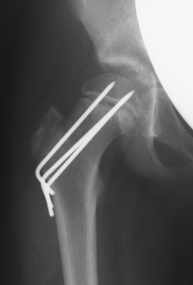

Epiphyseolysis capitis femoris

Die Epiphyseolysis capitis femoris ist ein Hüftkopfabrutsch in der Wachstumsfuge. Ein Abrutschwinkel bis 30° wird mit Drähten oder Schrauben versorgt. Bei einem größeren Abrutschwinkel muss meist eine Schenkelhalskorrekturosteotomie (OP nach Imhäuser) oder eine offene Reposition durchgeführt werden.

Da sehr häufig beide Hüftseiten betroffen sind, wird die Fixierung des Hüftkopfes immer beidseits durchgeführt. Die nicht betroffene Seite kann nach der Operation jedoch sofort wieder belastet werden.